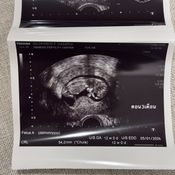

โดยวันนี้ (14 ก.ค. 68) เนย ได้โพสต์รูปถือภาพอัลตร้าซาวด์ลูกคนแรก ผ่านอินสตาแกรม พร้อมเขียนแคปชั่นข้อความเล่าไว้อย่างละเอียดว่า

"ช่วงนี้หาย ๆ ไปเพราะว่าเนยมีน้องแล้ว ในรูปคือประมาณ 3 เดือน ตอนนี้ก็เกือบจะ 4 เดือนแล้ว ท้องป่องแล้ว ต้องบอกว่าจะมีลูกคนหนึ่งไม่ง่ายเลย เข้าใจว่าตัวเองแข็งแรงสุขภาพดีมาก ดูแลตัวเองมาอย่างดีมาก ๆ อาหารการกินคือคลีน ไม่ดื่ม ออกกำลังกายสม่ำเสมอ นอนไม่ดึก แต่ปรากฏว่าเนยบ๊ายบายน้องไปถึง 2 รอบ จนแปลกใจมากจริง ๆ เลยตัดสินใจไปหาคุณหมอมิงค์ พอตรวจปรากฏว่าเนยและก็สามี มีโรคทางพันธุกรรมแฝงทั้งคู่ (เลยรู้สึกว่าก็โชคดีที่น้องบ๊ายบายไปถึง 2 รอบเพราะถ้ารอดมาชีวิตก็คงลำบาก) โอกาสที่เด็กจะออกมาสมบูรณ์มีแค่ 25% เท่านั้น ซึ่ง%ที่เหลือคือเป็นโรคกับเป็นโรคแฝงแบบเนยที่ใช้ชีวิตปกติจนโตได้ แต่เราก็จะมียีนที่ผิดปกติติดตัวส่งทอดไปสู่รุ่นอื่น ๆ ได้ ซึ่งเนยเลือกที่จะให้ลูกสมบูรณ์ 100% เลยดีกว่า เลยเริ่มทำ ICSI ทั้งคัดโครโมโซม ตรวจคัดโรค และหลังใส่ตัวอ่อนก็ทำ NIFTY อีก (คือต้องเพอร์เฟกต์ละมั้ย555) ต้องบอกว่าคุณหมอดูแลดีมาก ๆ ตั้งแต่วันแรกไปจนวันสุดท้ายของกระบวนการเลย รวมไปถึงพยาบาลทุกคนให้คำปรึกษาละรับฟังอารมณ์ของเราเป็นอย่างดี ส่วนขั้นตอนนั้นก็ใช้ความอดทน..55 ไม่เจ็บหรอกแต่จุกจิกเหลือเกิน ต้องกินยา สอดยา ฉีดยาตัวเองให้ตรงเวลาเสมอ ไปทำงานทำอะไรต้องรีบกลับให้ทันเวลาฉีดยา สำหรับเนยเป็นการทำ ICSI ครั้งแรกแล้วก็ประสบความสำเร็จเลย ไม่ต้องทำหลาย ๆ รอบให้ท้อใจ ตอนนี้น้องสมบูรณ์แข็งแรงมากแค่ 3 เดือนก็ดิ้นเก่งซะแล้ว ต้องขอบคุณคุณหมอมาก ๆ ที่ทำให้ทุกอย่างราบรื่นจริง ๆ"